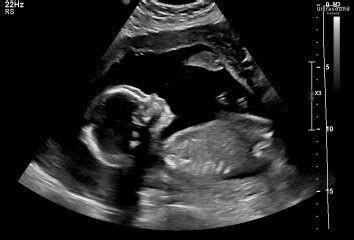

Hey there, expectant parents! Let’s chat about something that’s often on the minds of many of you in South Africa as you approach the halfway mark of your pregnancy journey: the 20-week anatomy scan . It’s a truly incredible moment, a chance to get a really detailed look at your little one, but it can also bring a mix of excitement and, let’s be honest, a bit of anxiety. The big question often lurking in the back of your mind is, “How common is bad news at the 20-week scan in South Africa?” We’re going to dive deep into that, guys, breaking down what this scan is all about, what ‘bad news’ actually means, and what to expect if any concerns pop up.

The 20-week anatomy scan , often simply called the mid-pregnancy scan or morphology scan , is a truly pivotal point in your prenatal care, especially here in South Africa . This isn’t just a quick peek; it’s a comprehensive, high-resolution ultrasound examination performed usually between 18 and 22 weeks of gestation . The primary purpose of this scan is to thoroughly assess the fetal anatomy, growth, and development, ensuring that everything is progressing as it should be. Think of it as your baby’s first really detailed health check-up, all while they’re still comfy inside you! During this scan, the sonographer or obstetrician will meticulously examine every major organ and body part of your developing baby. They’re looking at the brain, heart (checking all four chambers and major blood vessels – a super important part!), spine, kidneys, bladder, stomach, limbs, and even tiny fingers and toes. They’ll also measure various parts of your baby to ensure they’re growing at an appropriate rate, which helps confirm your estimated due date. Beyond just the baby, the sonographer will also assess other crucial elements of your pregnancy. This includes checking the position and health of the placenta, measuring the amount of amniotic fluid surrounding your baby, and evaluating the cervix. These factors are all vital for a healthy pregnancy and can flag potential issues early on. For instance, a low-lying placenta (placenta previa) or insufficient amniotic fluid might require further monitoring. So, as you can see, this scan is incredibly comprehensive. It’s designed to pick up any significant structural anomalies or developmental issues that might affect your baby’s health. While it can detect a large percentage of major abnormalities, it’s important to remember that no scan is 100% foolproof, and some conditions simply cannot be seen or develop later. However, for many families in South Africa , this scan provides immense reassurance, confirming that their little one is thriving. It’s also often the moment many parents find out the sex of their baby, if they choose to know, adding another layer of excitement to this significant appointment. So, when you walk into that ultrasound room, know that you’re not just seeing a cute picture; you’re getting a vital health assessment that empowers both you and your healthcare team to provide the best possible care for your pregnancy journey. This thorough examination is a cornerstone of modern prenatal care and an invaluable tool for ensuring the well-being of both mother and baby throughout the remainder of the pregnancy, and even preparing for birth and beyond here in South Africa .